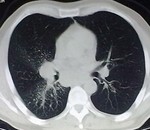

Оказываетя, что за год до этого пациенту была удалена опухоль на бедре, гистологически синовиальная саркома. Было произведено КТ ОГК. Подтвердили пневмонию, мета в позвоночник.

Не зная, что была такая операция (больной вначале это притаил, видимо не хотел к этому возвращаться) я предположил БАР, но компъютерщики развеяли мои подозрения. Поэтому я бы хотел знатоков КТ-дела проанализировать сканы, все ли там в порядке с корнем и т.д.

Пневмонии тут нет никаким боком. Не было КТ - высказался бы за БАР. На КТ, в легких -типичный раковый лимфангаит (кстати, слева тоже, еще чуть-чуть и полыхнет). Так что, 100% метастазирование. И это кроме очевидного метастаза в позвонок. А корень надо оценивать в "медиастинальном" окне.